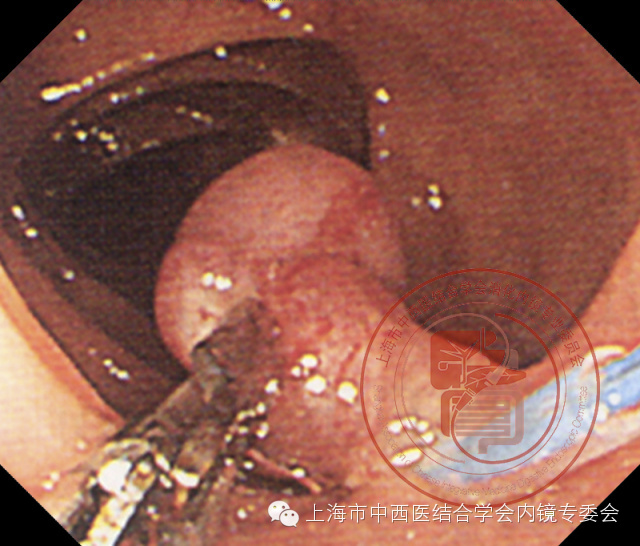

双钳道带蒂息肉尼龙套扎操作

5、当确认蒂部血供被阻断后,嘱助手放开鼠齿钳。

松开鼠齿钳

6、金属圈套器套住息肉,用鼠齿钳继续咬夹息肉端部向上向左侧提拉,确定金属圈套器在蒂部满意位置后高频电切除息肉。

高频电切除息肉

7、切除后的创面发白。

创面